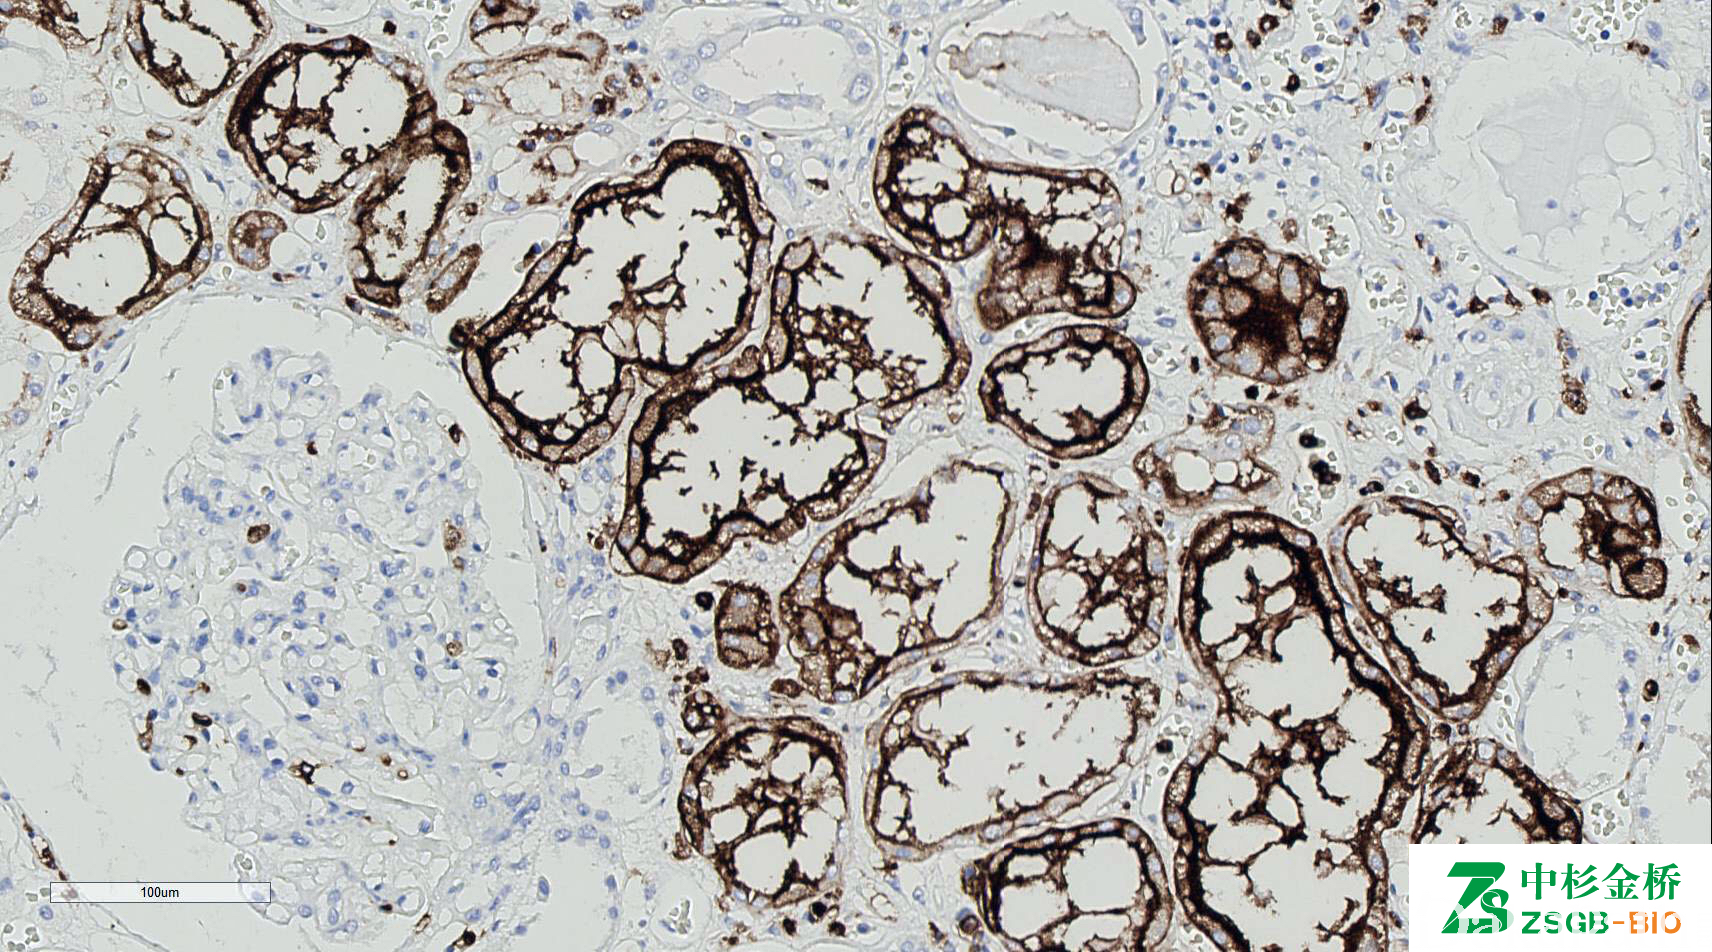

CD15

别名: LeuM1, Lewis X, 3-fucosyl-N-acetyl-lactosamine

是一种碳水化合物,标记何杰金 R-S 细胞,髓细胞白血病/肉瘤(是相对成熟髓细胞的标记物; CD117 标记相对幼稚的髓细胞,而 MPO 是相对广谱的髓细胞标记物)。腺癌阳性,可用于与间皮瘤( -)鉴别,但效果不如 BerEP4 等其它腺癌标志物。

信号定位: 胞膜、胞质

几乎全部阳性(≥95%的病例阳性): 结直肠腺癌、乳头状肾细胞癌、膀胱透明细胞癌、毛发上皮瘤、大汗腺腺瘤、卵巢透明细胞癌、皮肤大汗腺腺癌、胸腺乳头状癌、睾丸交界性乳头状浆液性肿瘤、睾丸浆液性囊腺瘤、涎腺小管腺瘤、肾嗜酸细胞瘤、皮肤小汗腺乳头状腺瘤